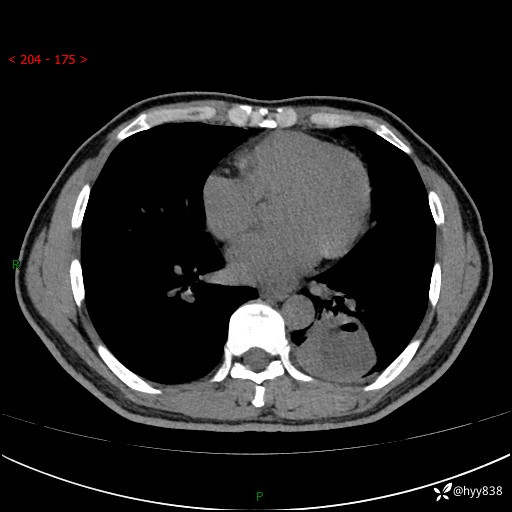

57岁/男,间断痰中带血1月余。纤支镜没有取到东西,穿刺轻松搞定---结果公布~

现病史:患者1月余前无明显诱因出现咯血症状,为痰中带血,量不大,伴轻度咳嗽,2024-3-26于当地市中医医院行胸部CT示:左肺下叶占位性病变。现患者仍有咳嗽不适,无发热乏力,无腹泻、便秘,无咳嗽,无头晕、无双下肢水肿等伴随症状,未行特殊治疗,今日患者再次出现咯血症状。患者为求进一步诊治,遂入我院,门诊以“肺脓肿”收入我科。 患者病程中,精神食欲可,二便正常,体力体重较前变化不明显。

增强